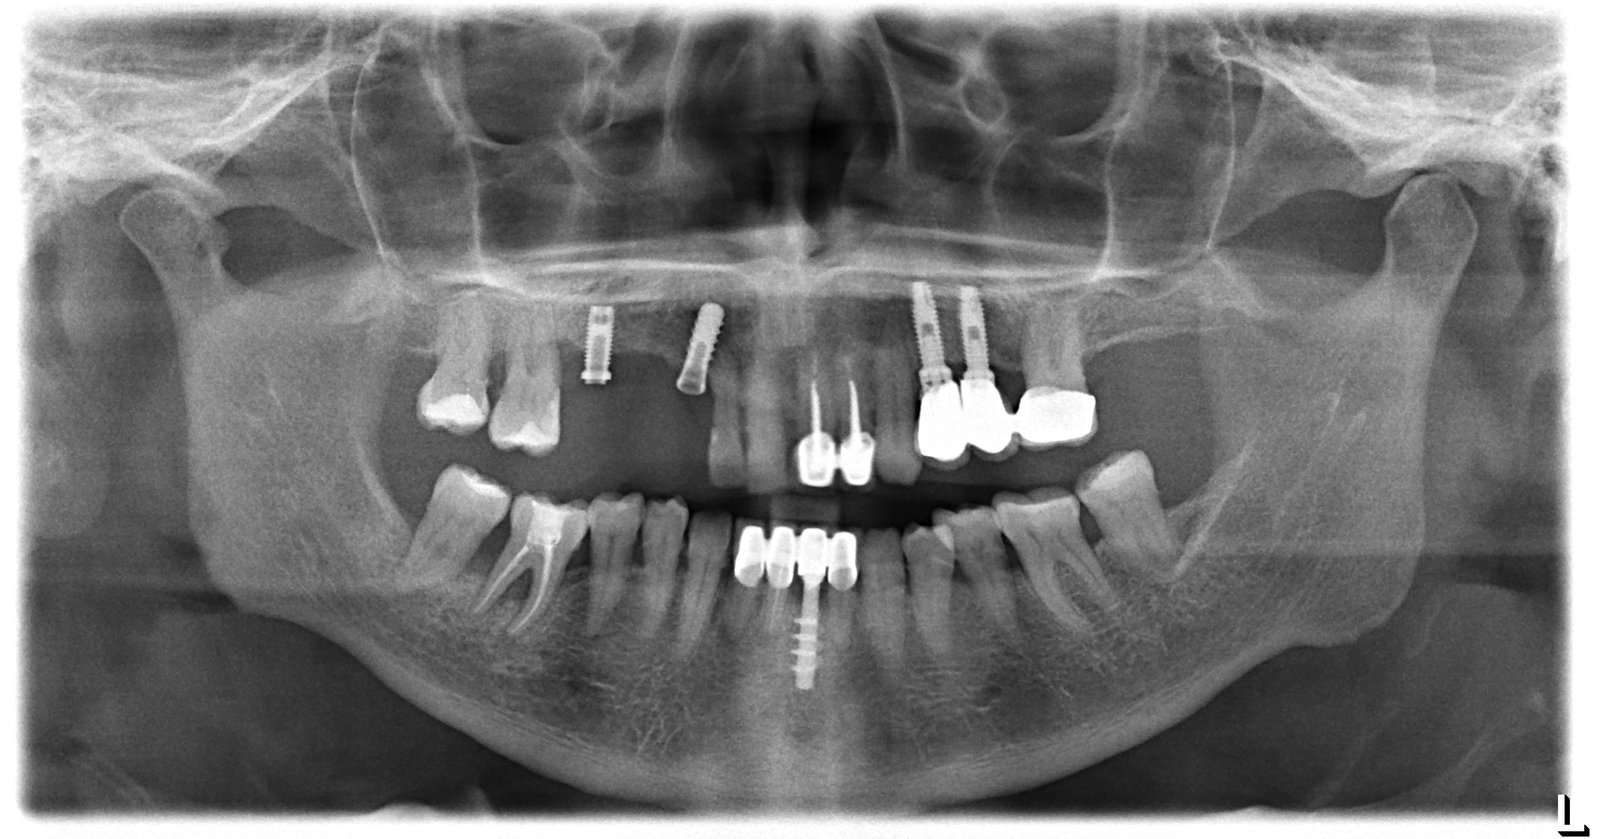

Buenas, acude esta mujer a mi clínica para rehabilitar lo que le queda en maxilar superior. El 13 y el 23 van a ser exodonciados y la idea de la [...]

es un caso de idental, que ha cerrado y ha dejado a los pacientes con el trabajo pagado y a la mitad, tengo varios casos y me gustaria saber con [...]